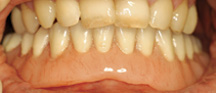

Missing a tooth ? An Implant can replace that missing tooth in no time. Modern dental implants are precision devices, the most common type is a titanium screw that is anchored into the jawbone where it serves as post for a custom-made tooth crown. Once the crown is in place, you may not be able to tell it apart from your natural teeth.

Missing teeth and loose dentures make too many people sit on the sidelines and let life pass them by. However, today’s modern treatment plans can replace everything from a single missing tooth to a completely missing arch. Ask your dentist or dental specialist about the different dental implant options that are available to you. Don’t let another day go by without taking this important first step to restoring your confidence and your smile!

Losing one or more of your teeth starts a chain of events that can have dire physical and cosmetic consequences. The most obvious result is a gap in your smile. Less obvious is the loss of chewing function and the inability to eat a complete diet that can result from tooth loss. While these are certainly serious issues, a potentially bigger problem lies hidden beneath the surface: bone loss.

Your jawbone needs the chewing action of the teeth to stimulate it and keep it strong. Otherwise it will begin to disappear (atrophy) in the same manner that the unused muscles beneath a cast supporting a broken bone get smaller. Without the support of your teeth and facial bones, your face will begin to look prematurely aged. The good news is that tooth replacement with dental implants offers a solution to help prevent bone loss..